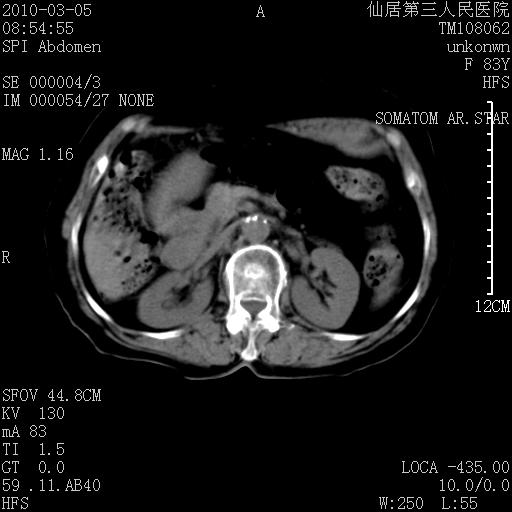

标题: CT24879:腹直肌病变。在线等。

女性,83y,腹痛一周。

增强看看,mfh可能性大,次之可考虑血肿、bfh、转移瘤、神经纤维瘤、侵袭性韧带样纤维瘤等。肝内钙化灶,右肾结石。

支持腹壁纤维肉瘤